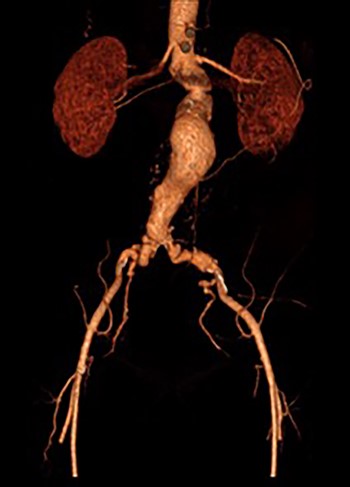

Post-lysis CT scanning showing fully re-canalized aorto-iliac system.

The patient was transferred to the high-dependency unit for observation during the thrombolysis. After 4-h, the patient was taken back to Interventional Radiology department for a check angiogram (Fig. 3). This demonstrated a fully re-canalized aorto-iliac system with no distal thrombotic or embolic complications. The thrombolysis infusion was stopped at this stage. In the post-operative period, anticoagulation has been continued with Apixaban. A CT scan 6 weeks post-procedure has confirmed ongoing patency of the endograft with no visible thrombus (Fig. 4).